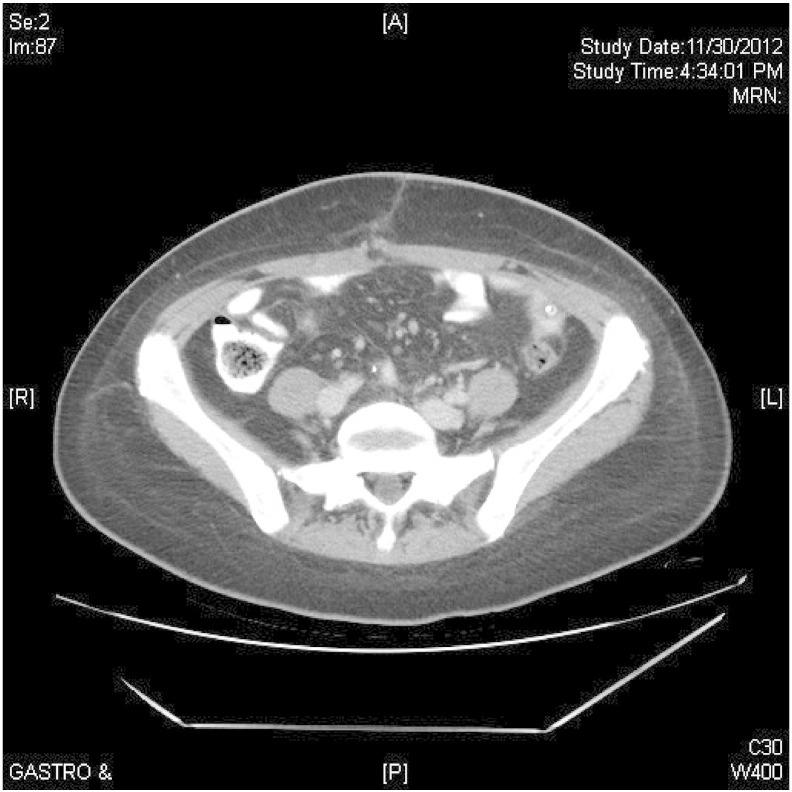

Primary debulking surgery for metastatic cervical adenocarcinoma: A case report.

•The case presented is that of a primary debulking surgery for presumed ovarian cancer.•Final pathology revealed diffusely metastatic endocervical adenocarcinoma.•After primary chemotherapy, the patient has remained disease-free 30 months after surgery.